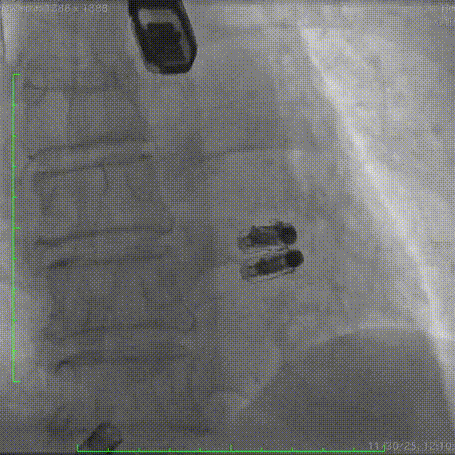

术后DSA